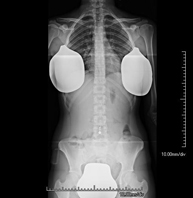

Técnica mediante la cual, utilizando rayos X, se obtienen imágenes de toda la columna vertebral para su estudio, valorando especialmente la presencia de escoliosis y dismetrías pélvicas.

Técnica mediante la cual, utilizando rayos X, se obtienen imágenes de toda la columna vertebral para su estudio, valorando especialmente la presencia de escoliosis y dismetrías pélvicas. - Telemetría EEII (Extremidades Inferiores)

Técnica mediante la cual, utilizando rayos X, se obtienen imágenes de la totalidad de ambas extremidades inferiores para su estudio, valorando especialmente la presencia de dismetrías entre ambas. - RX Extremidades